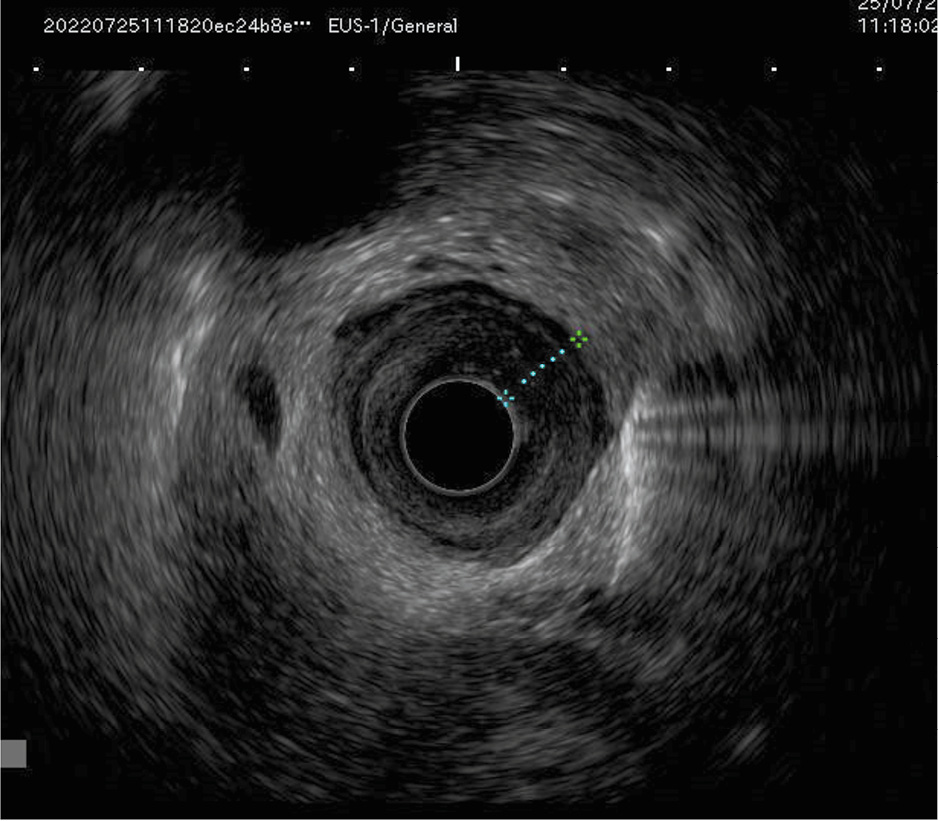

Для иллюстрации последнего приводим рис. 1, 2, где представлена эндоскопическая и эндосонографическая картина стадии Т4а.

Рис. 2. Эндосонографическая картина опухоли нижнегрудного отдела пищевода. На фото: сканирование из просвета пищевода. Инвазия опухоли на все слои стенки пищевода. / Fig. 2. Endosonographic image of a lower thoracic esophageal tumor. Pictured: a scan from the esophageal lumen. Tumor invasion into all layers of the esophageal wall.